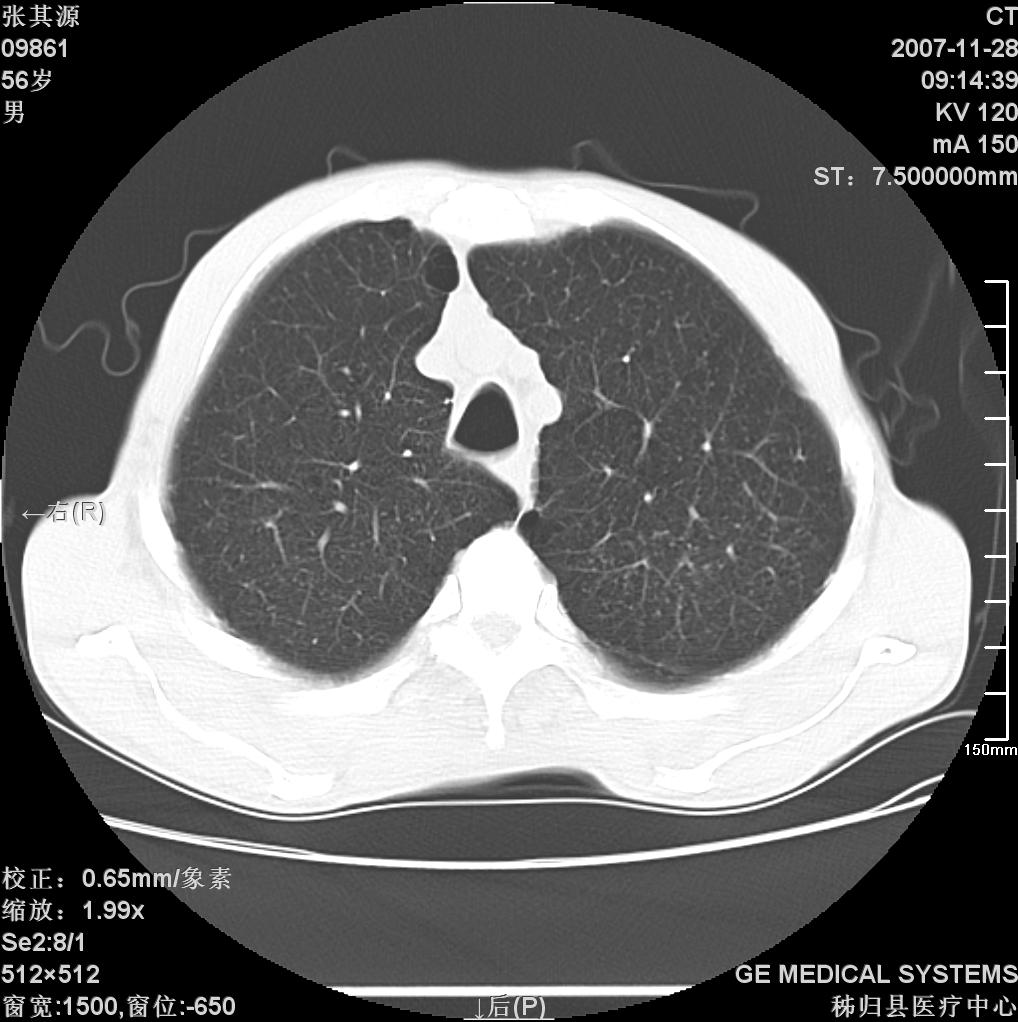

患者因阻塞性黄疸入院,发病前10天持续中等程度发烧.术前检查发现两肺弥漫性病变,请各位大虾会诊,除了考虑急性血源性肺结核外,还有其他什么疾病可能.

两肺另见略大结节,结合病史,应考虑转移,有腹部片吗?肺内表现可有:结核?甲状腺癌肺转移?肺泡癌?

双肺多发粟粒样病灶,右肺胸膜下结节样病灶,气管前腔静脉后及隆突下均见肿大淋巴结,结合胆道肿瘤病史首先考虑转移。另外心影密度略低,时间格显示,是否有贫血?查明白再手术吧!